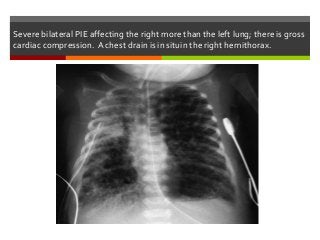

Severe bilateral PIE affecting the right more than the left lung; there is gross

cardiac compression. A chest drain is in situin the right hemithorax.

Severe bilateral PIEaffecting the right more than the left lung; there is gross cardiac compression. A chest drain is in situin the right hemithorax.